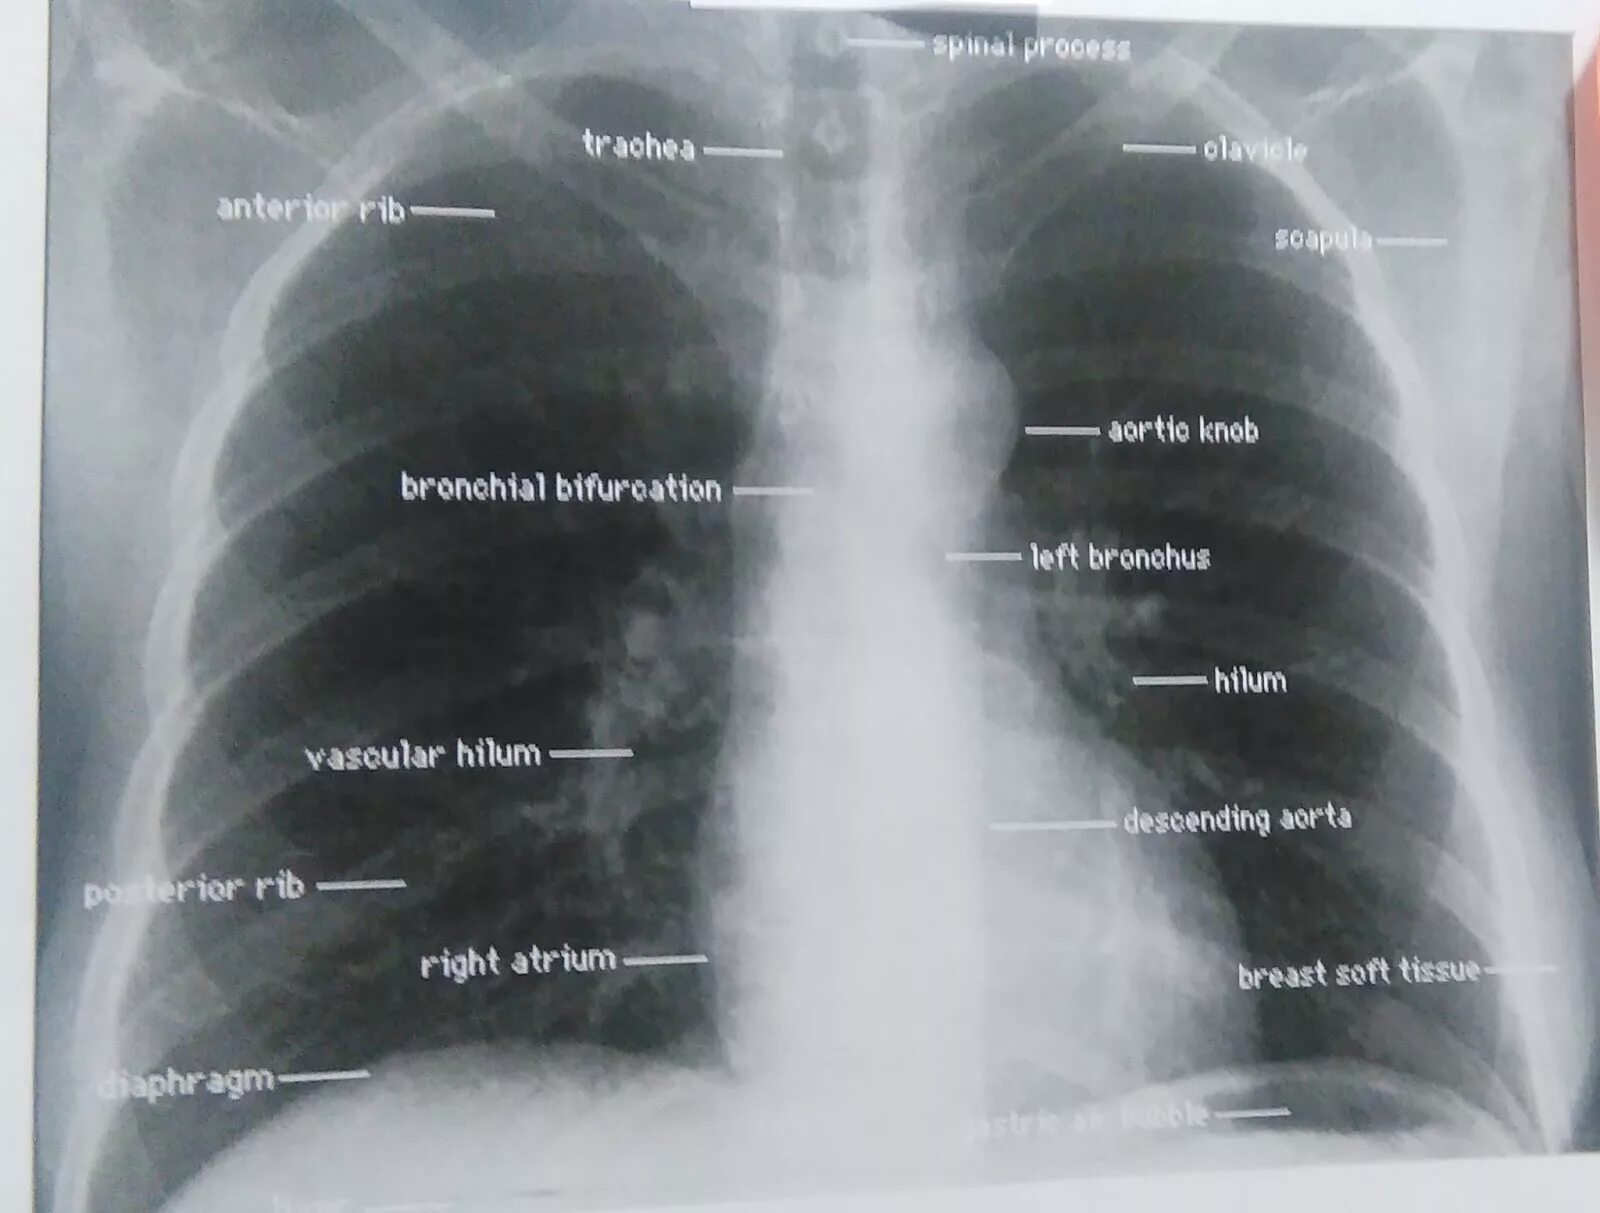

Что значит аорта уплотнена на флюорографии